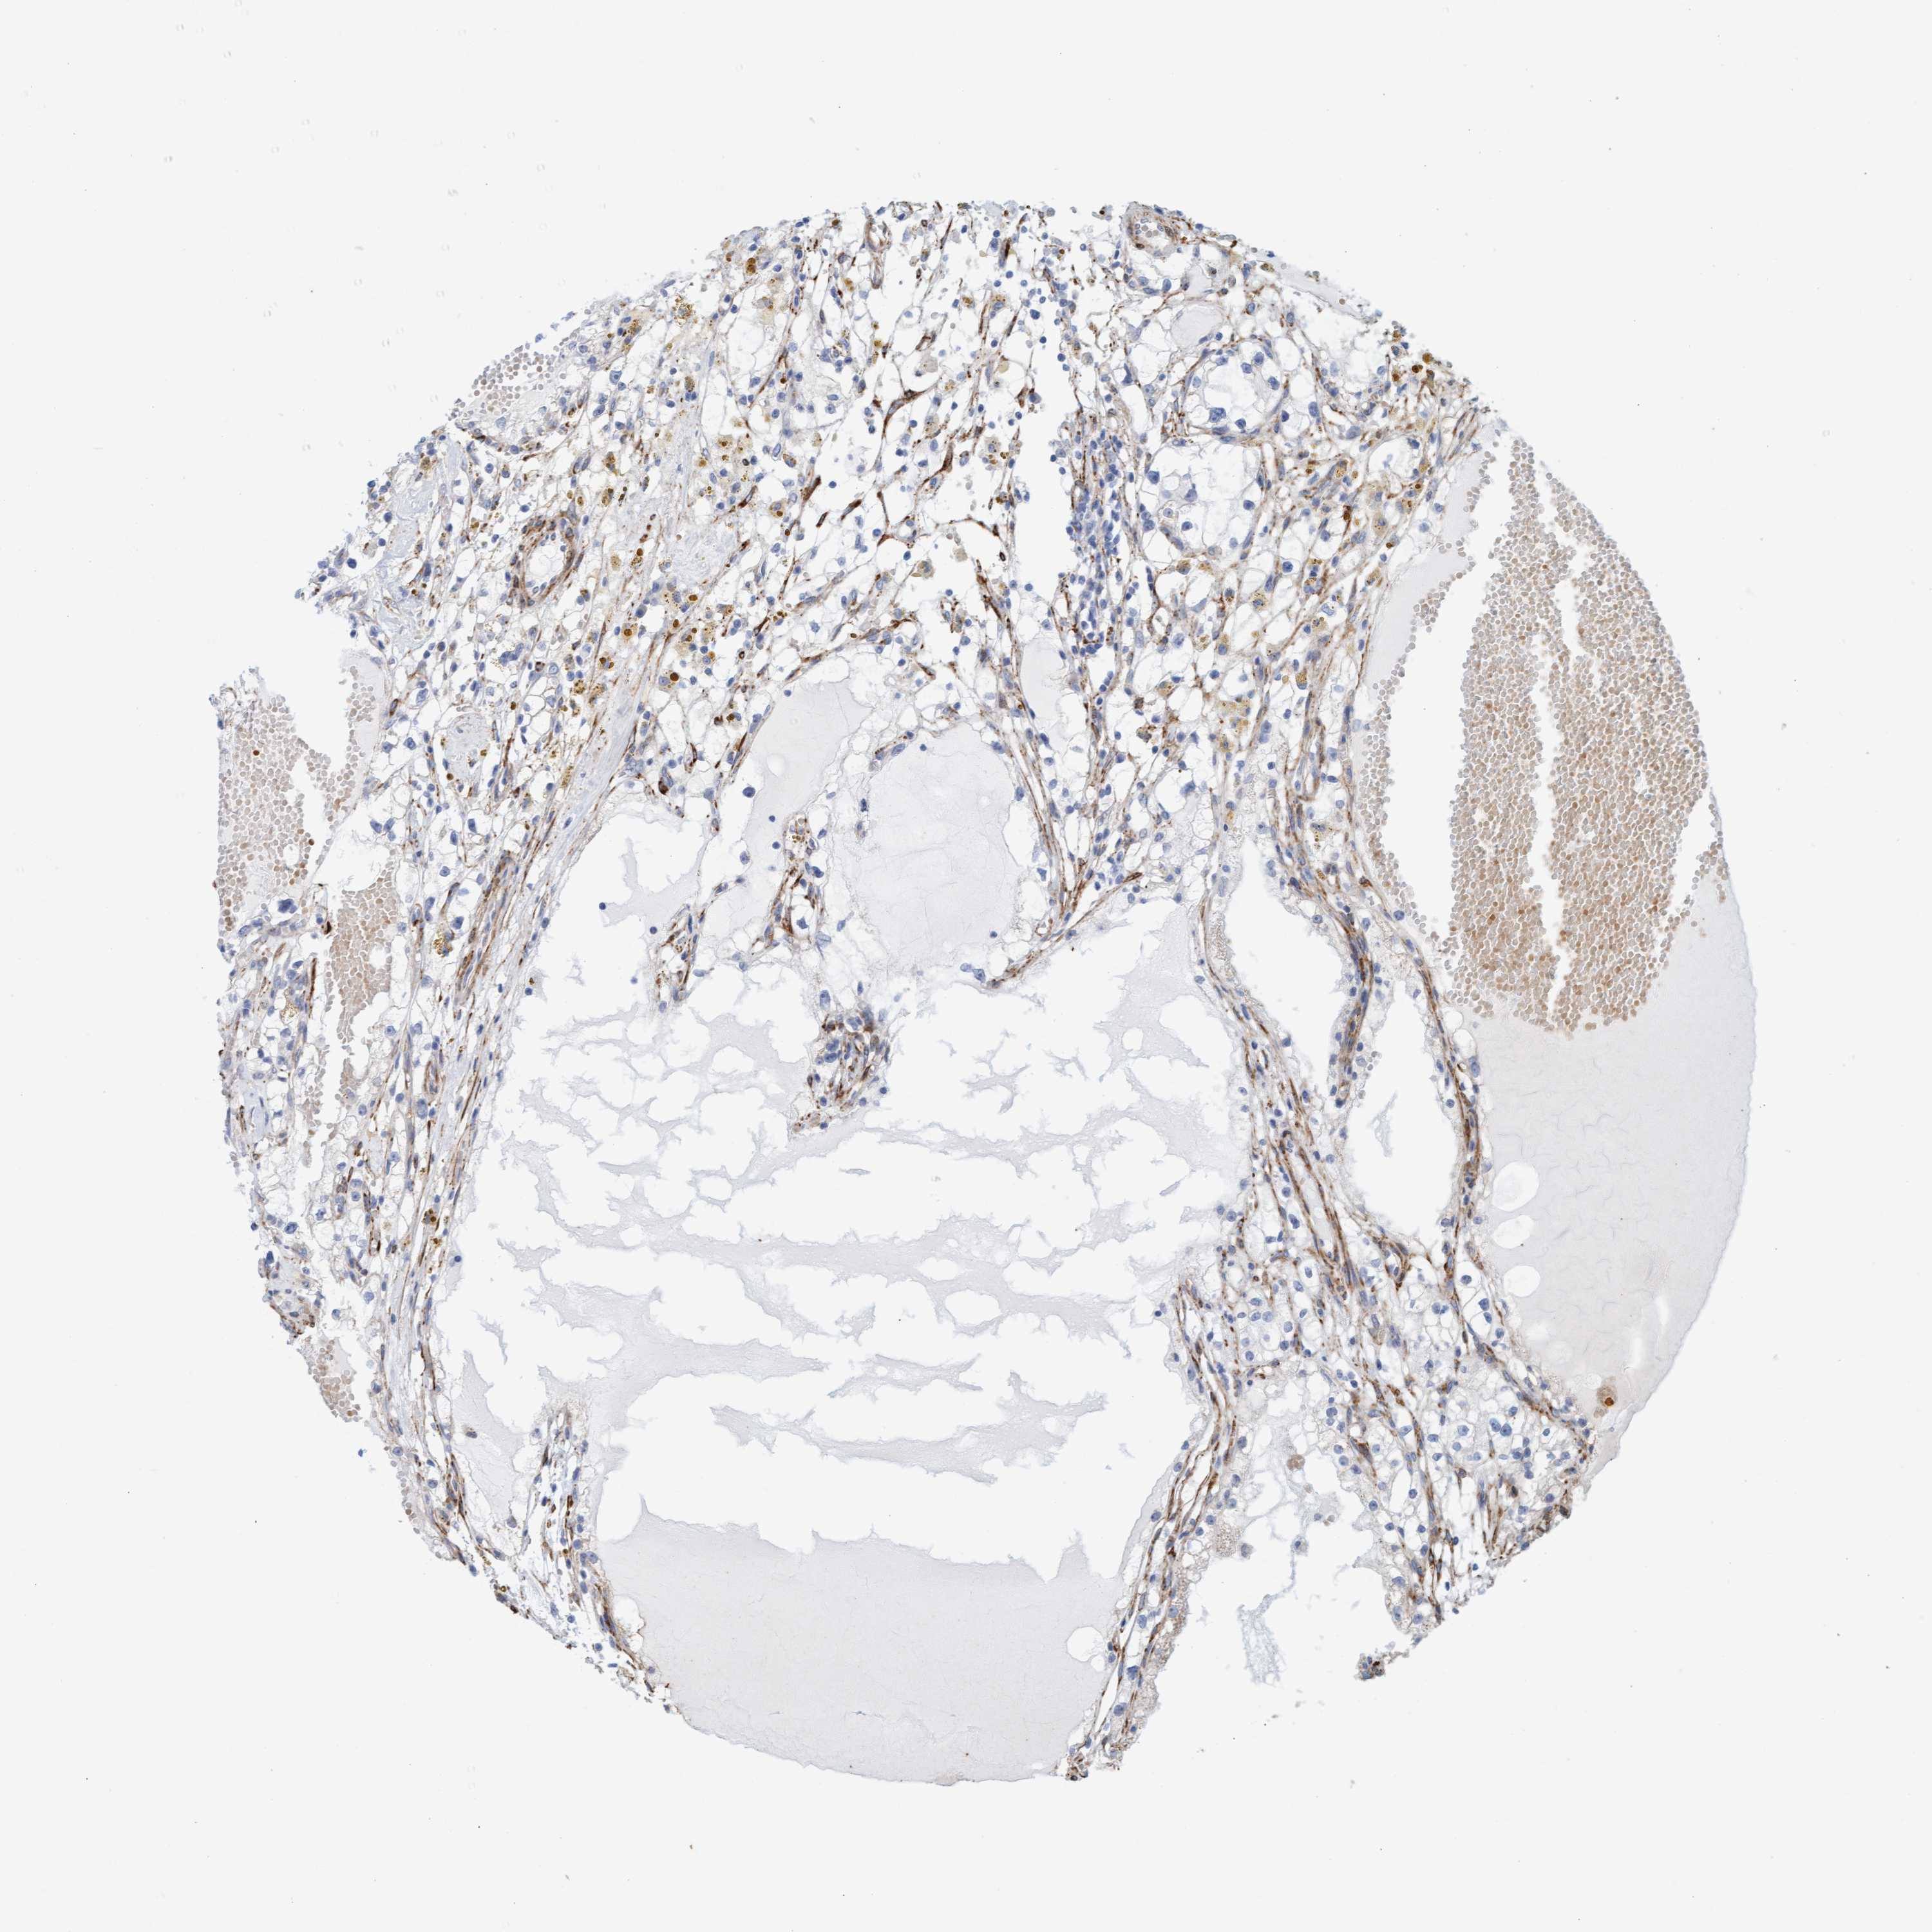

CANCER RENAL CANCER Show tissue menu

KICH TCGA KIRC TCGA KIRC VALIDATION KIRP TCGA PROTEIN RCC CPTAC PROTEIN EXPRESSION